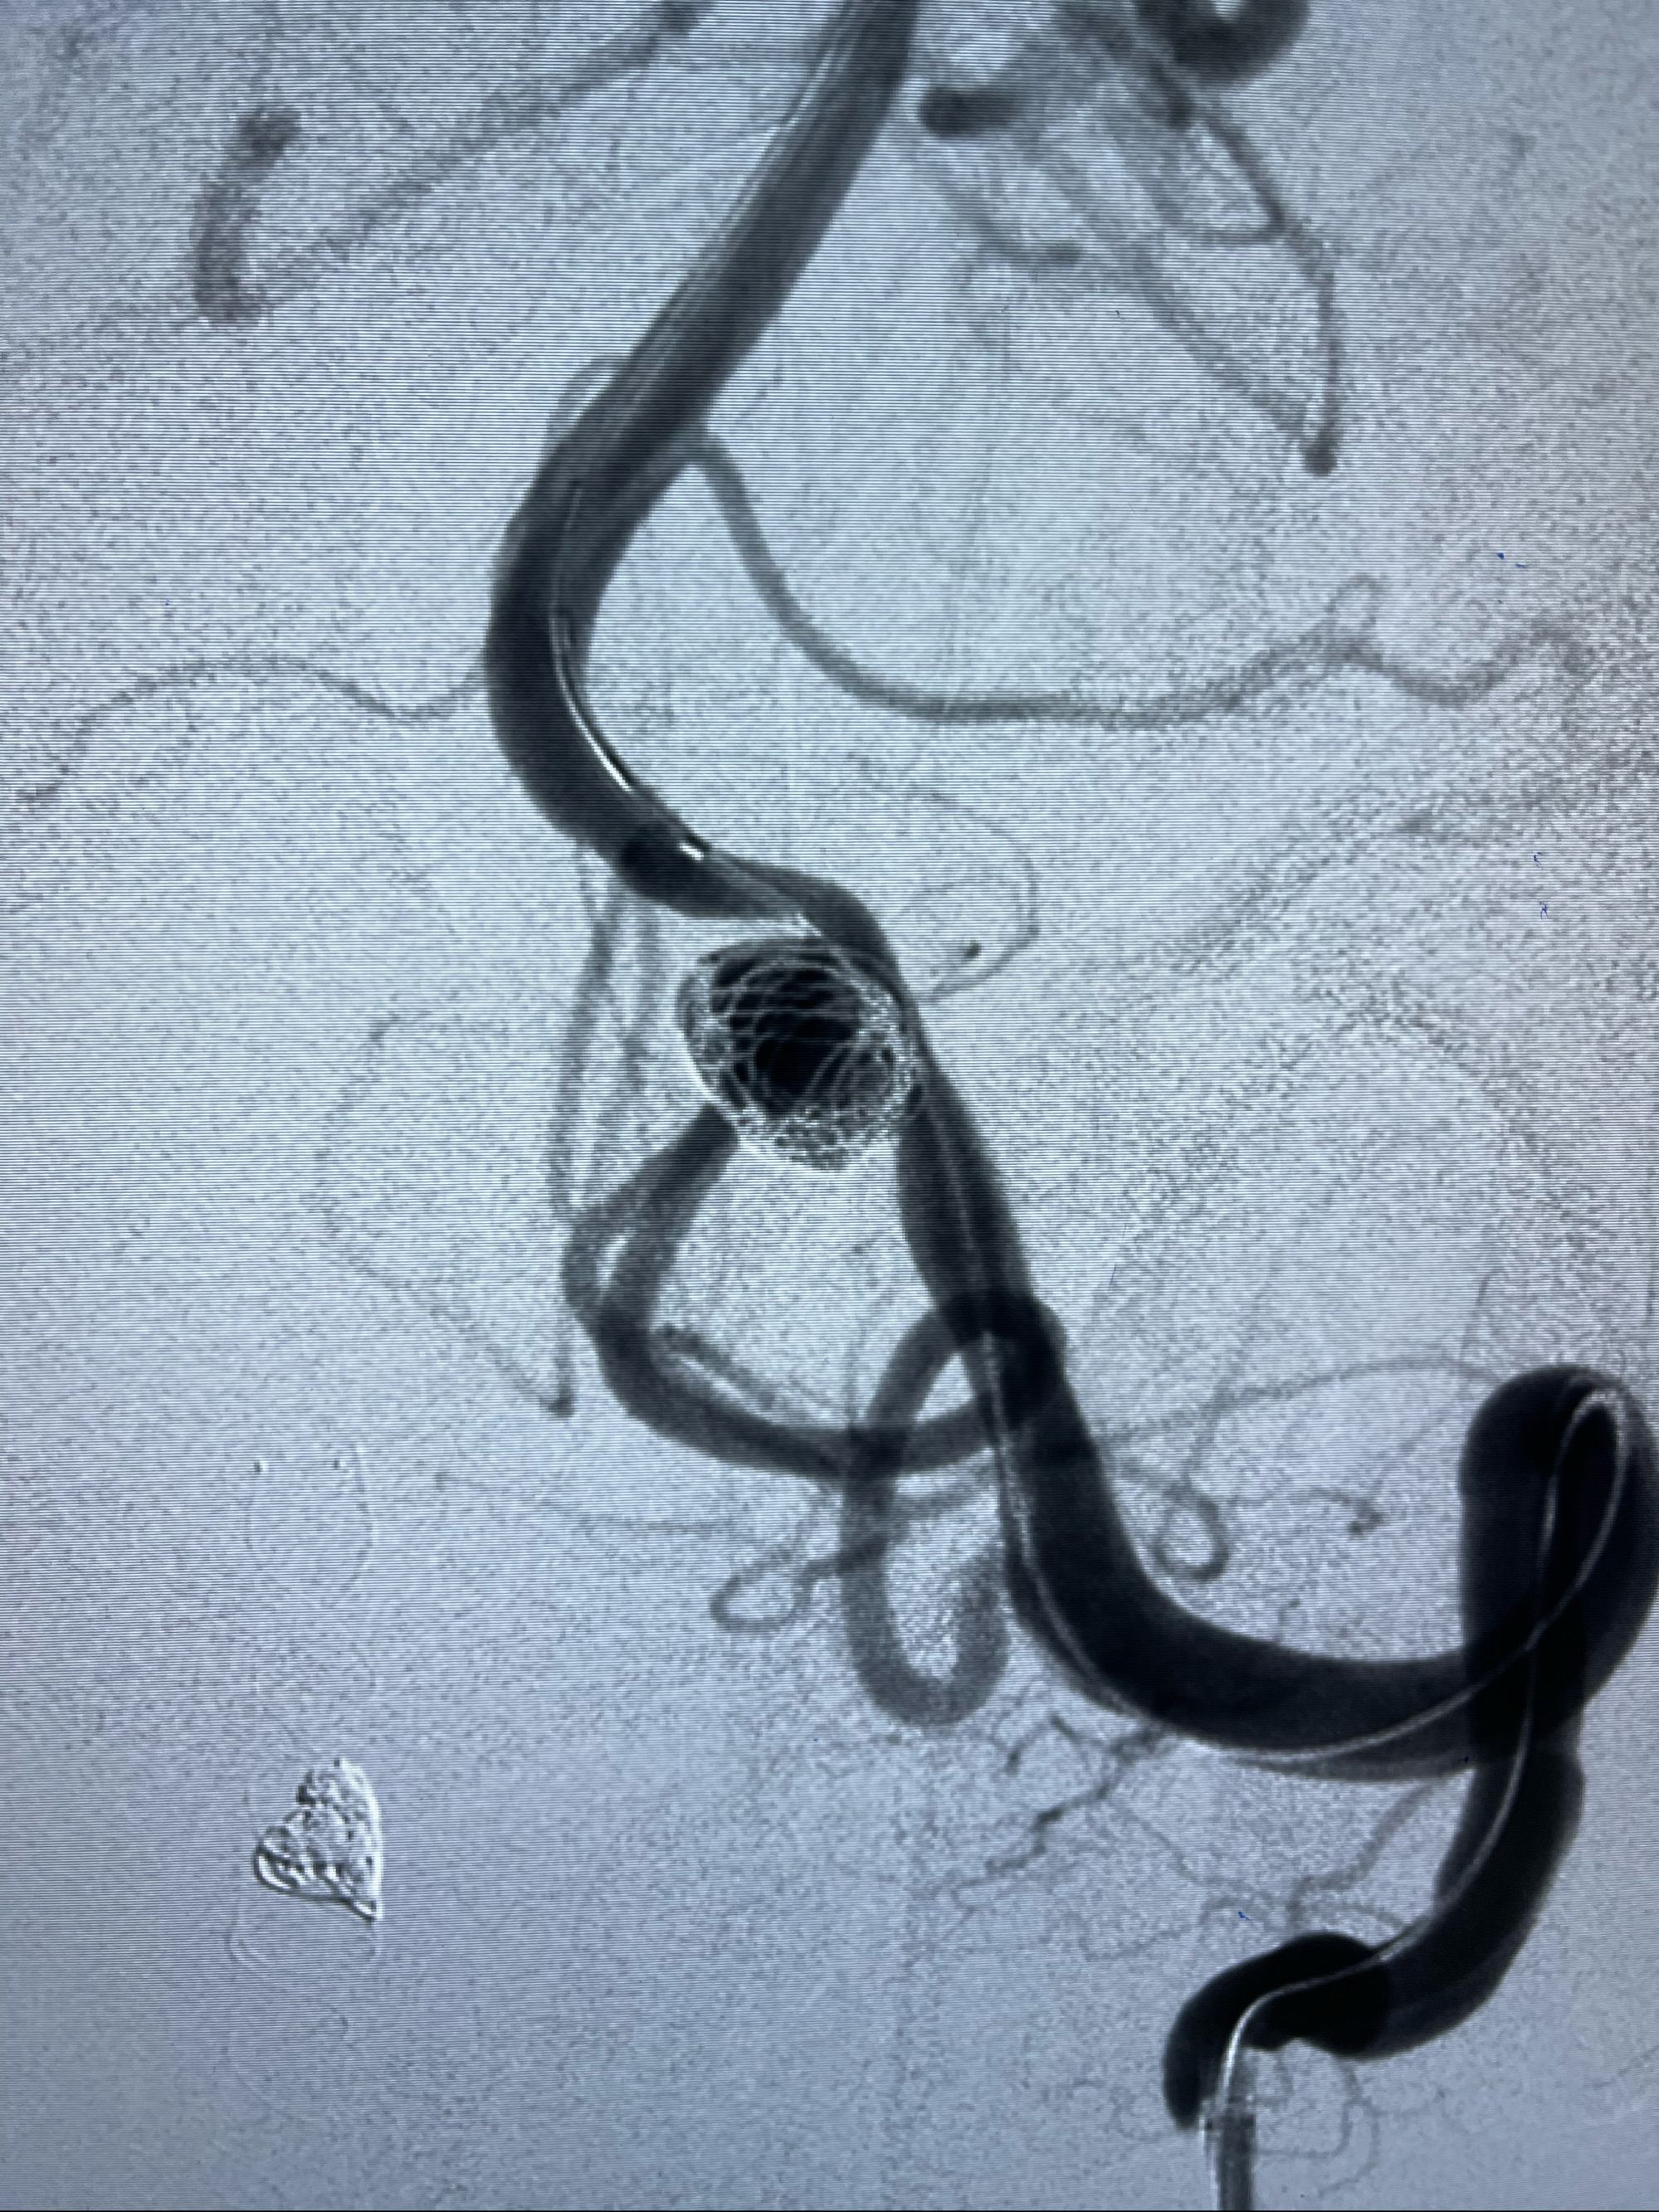

右侧颈内动脉夹层动脉瘤Lvis5.5-20mm支架辅助栓塞

工作角度造影

即刻造影

支架到位